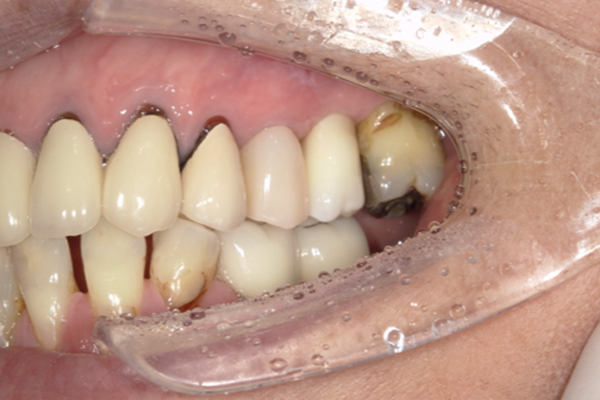

| 主訴 | 奥歯で噛めない、顎が痛い |

|---|---|

| 治療内容 | 奥歯のインプラント治療、前歯・奥歯の被せ物治療 |

| 治療期間 | 6ヶ月 |

| 治療費 | 350万円 |

| 治療リスク | 被せ物をつけた初期の段階で歯がしみることがある(時間とともに改善する) インプラント治療後に3日程度痛みと腫れを伴うことがある |